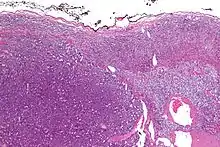

| Micrograph of an adrenocortical carcinoma (left of image – dark blue) and the adrenal cortex it arose from (right-top of image – pink/light blue). Benign adrenal medulla is present (right-middle of image – gray/blue). H&E stain. | |